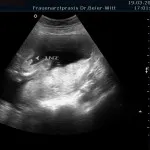

Frühschwangerschaft:

Ultraschall_5